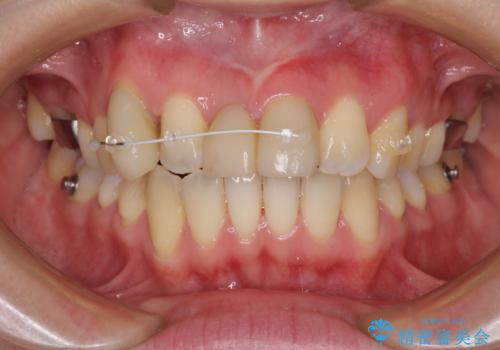

- インビザライン

本来であれば積極的に小臼歯を抜歯して口元を下げても良いのですが、前歯を1本抜歯しないといけなくなったため、非抜歯矯正をインビザラインを用いて行うこととしました。